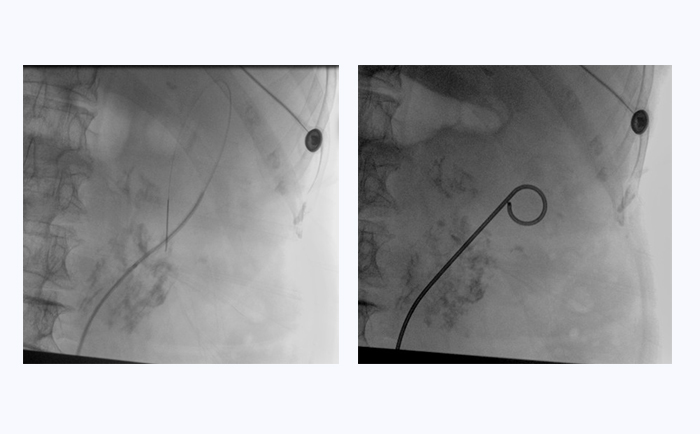

患者采用結(jié)石位進(jìn)行該手術(shù)。全麻后,操作輸尿管鏡從尿道進(jìn)入膀胱,通過(guò)鏡下觀察,找到輸尿管開口。此時(shí),在普愛醫(yī)療大平板一體式C形臂透視引導(dǎo)下,穿入導(dǎo)絲,到達(dá)腎盂并確認(rèn)位置,同時(shí)配合輸尿管鏡,找到狹窄部位。接下來(lái),同樣在透視引導(dǎo)下,沿導(dǎo)絲插入雙J管支架,當(dāng)支架兩端到達(dá)相應(yīng)位置后,抽出導(dǎo)絲和輸尿管鏡,完成手術(shù)。

普愛醫(yī)療大平板一體式C形臂臨床圖像